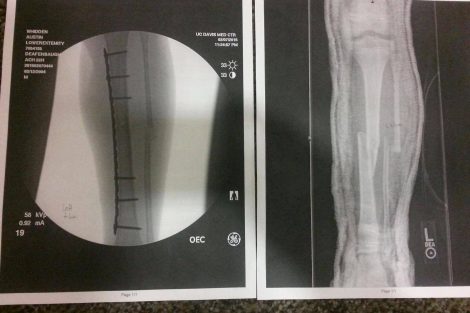

Austin was rushed to the UCD Med Center in Sacramento, where he underwent over 4 hours of surgery to repair the horrifying list of injuries…Broken right femur, Broken right ankle, Broken left tibia and fibula, multiple cuts and bruises to his arms and even his chin.

I spoke with Austin’s mother Ashley Whidden, who said that doctors repaired the injuries with metal plates and screws. The x-rays are horrifying.

Ashley said that he’ll have to have surgery again in 9 months to remove the plates and screws. Austin is resting comfortably, sleeping a lot, and even smiling at the pretty visitors.